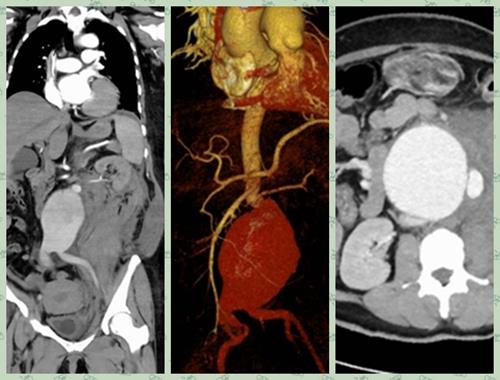

普外一科医生雷跃华等人早在一旁严阵以待,立即联系CT室急诊CTA检查,结果提示患者动脉瘤随时有破裂的可能,时间就是生命,情况十分危急。从CT上来看,患者动脉瘤瘤体紧贴双肾动脉,瘤颈短且扭曲,丧失腔内介入治疗机会,雷跃华立即将情况报告给了主任杨玉辉、副主任魏健。得知情况,杨玉辉立即做出指示,患者病情危急,必须立即手术,抢救患者生命。

手术中,发现患者腹膜后出现巨大血肿,约30x15cm大小,瘤体及腹腔内大量积血。时间紧急,立即用血管阻断钳紧贴肾动脉阻断血流,切开瘤体见瘤体后壁一长约6cm破口,成功切除动脉瘤体,并用人工血管进行腹主动脉及双侧髂动脉吻合,吻合口无出血。